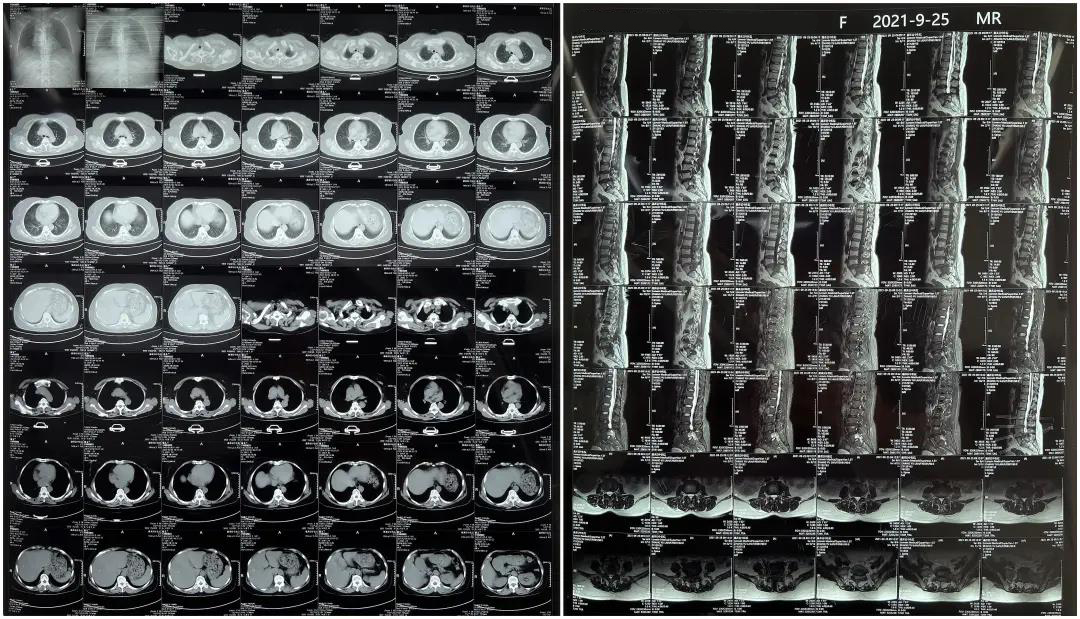

術(shù)前患者核磁共振圖像

顯示L3/4、L4/5椎間盤突出,L5-S1水平椎管內(nèi)占位